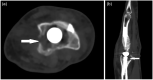

Metal-on-metal disease (MOMD) is a rare condition following arthroplasty and has predominantly been reported following hip and knee replacement. Isolated case reports exist with respect to MOMD following total wrist arthroplasty-however, the literature remains limited. Here, we present the history and radiographic and histopathologic features of such a case, and summarize the literature and provide management recommendations.